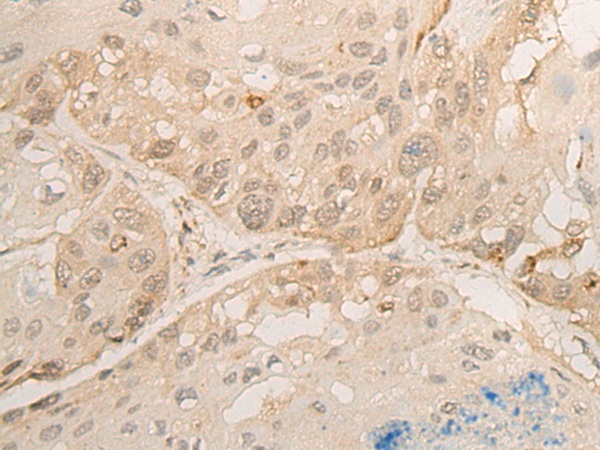

分类: 科研抗体货号: P06414别名:应用: IHC反应种属: Human